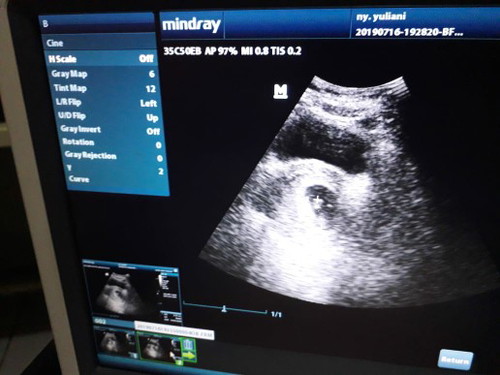

usg

Bun waktu bulan juni saya usg trus saya dinyatakan positif hamil dn katanya usia kehamilannya 9minggu itu kata bidan di RS, lalu kmarin saya coba usg lagi di beda bidan dan hasilnya ini tp kata bidannya usia kehamilan saya baru 8minggu, menurut bunda disini yg sudah berpengalaman usg kalo gambar seperti itu usia brp minggu ya bun ? Saya jadi bingung